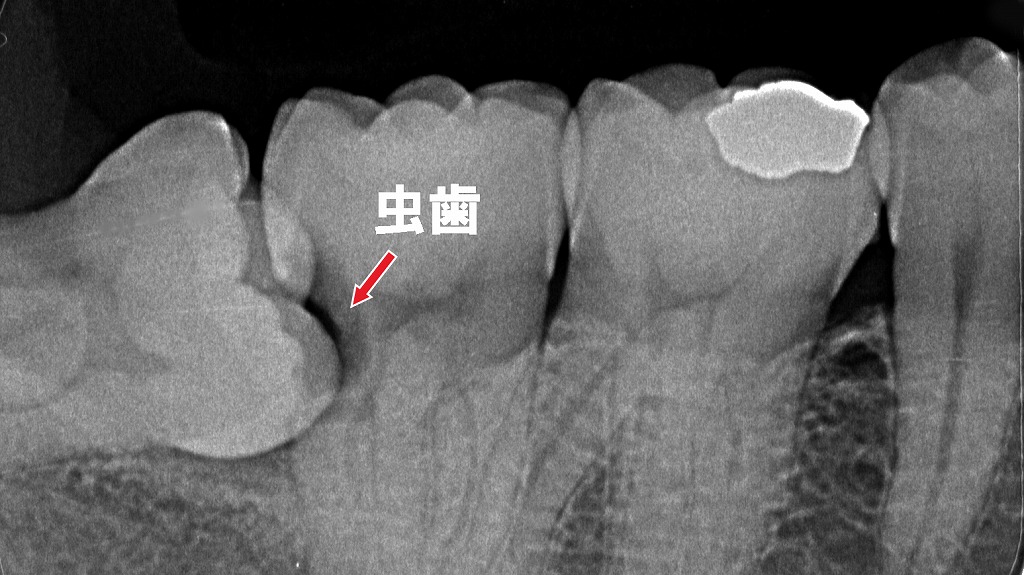

③ 親知らずの炎症(智歯周囲炎)

親知らずが半分だけ生えていると、歯と歯ぐきの間に汚れがたまりやすく、細菌感染で頬が腫れることがあります。

口が開けにくい・喉の奥まで痛むときは、炎症が強いサインです⚠️

画像のように、親知らずが手前の歯と密接していると汚れが溜まりやすく、強い炎症や腫れを引き起こします。

さらに、手前の歯の側面には虫歯もできやすく、痛み・腫れ・口が開きにくいといった症状につながります。